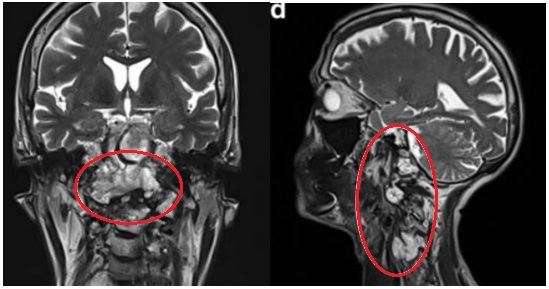

图2:颅颈交界区肿瘤手术治疗策略分析,肿瘤的旁正中部分可以通过经鼻内镜手术切除。枢椎齿状突周边肿瘤(A和D处红色圆圈)、侵犯硬膜内部分的肿瘤与后循环接触(B和E处蓝色圆圈)和先前乙状窦后入路手术的粘连(C和F处黄色圆圈),这些部位的肿瘤更适合二期远外侧开颅手术。